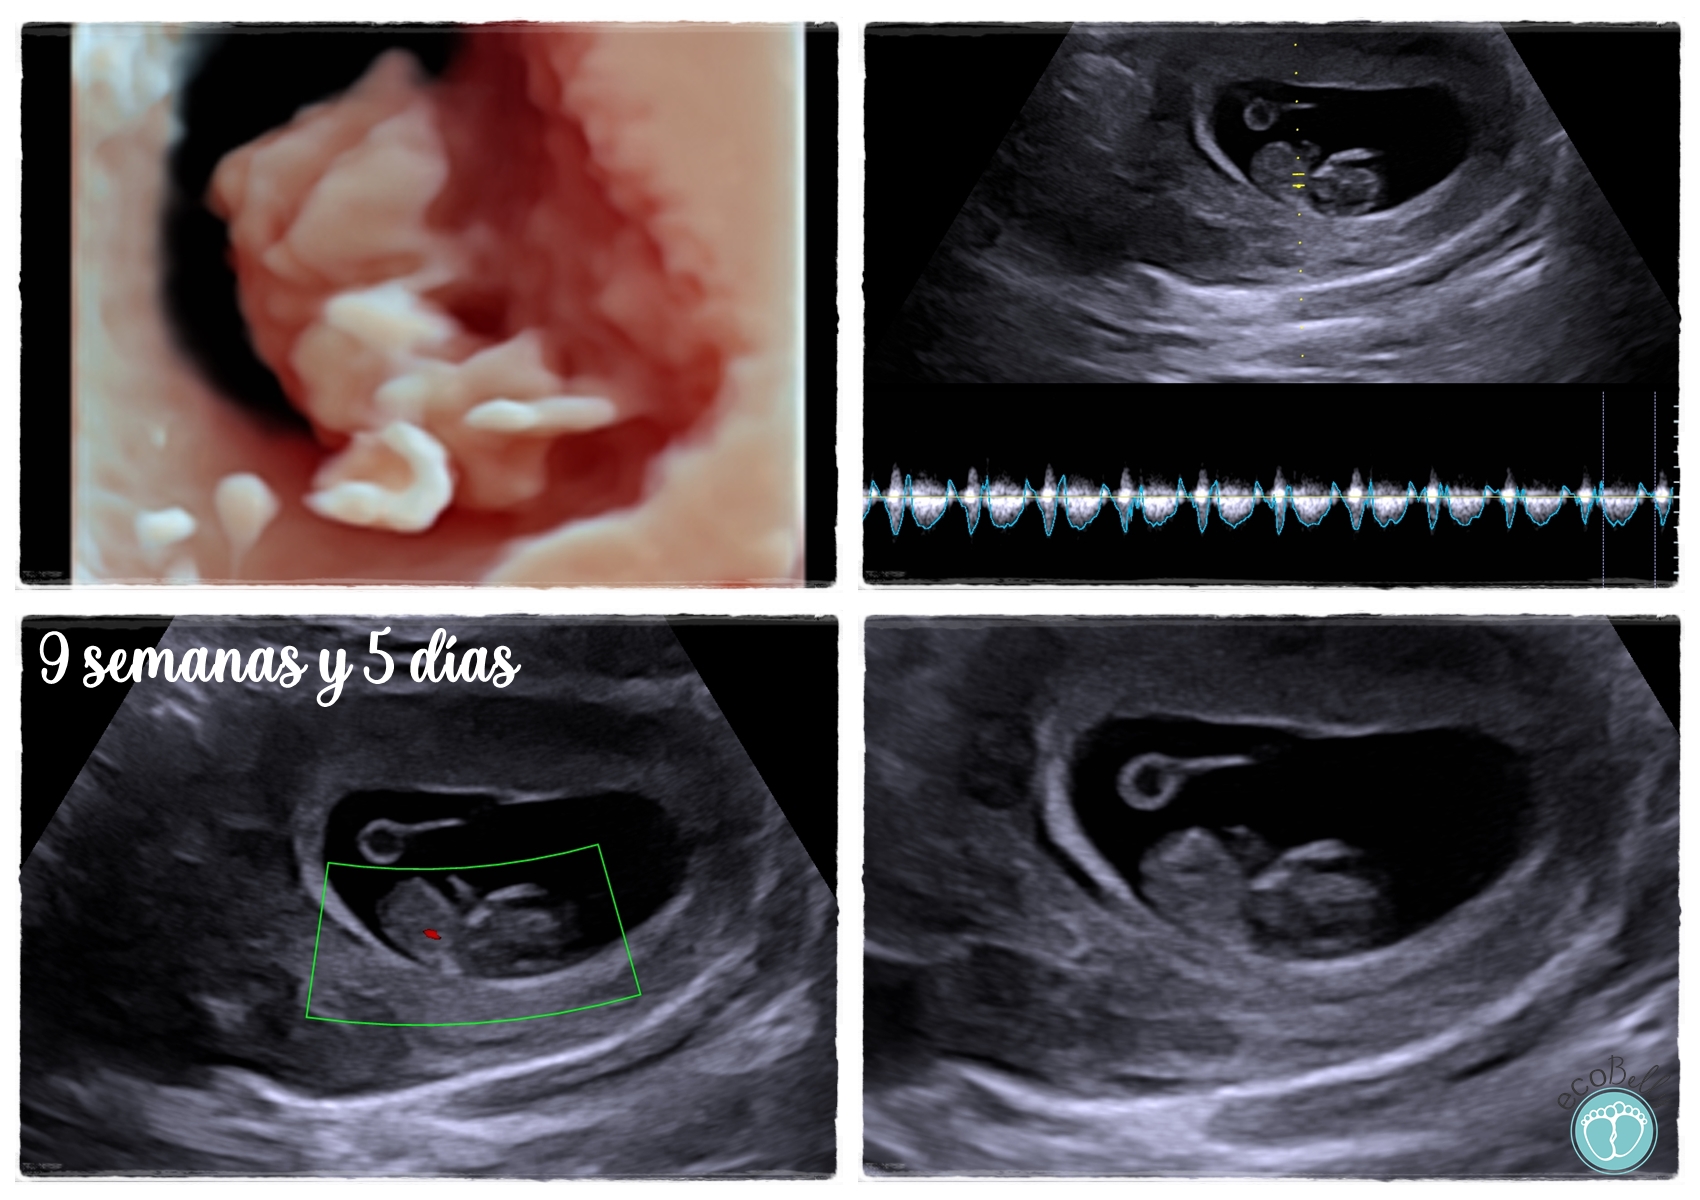

Con nuestro servicio Eco Latido, podrás conocer sus primeros latidos a partir de la semana 8 de embarazo, esa sensación única e inolvidable, adrenalina en unos pocos segundos.

Recomendamos realizar la Eco Latido a partir de la semana 8 de embarazo. En este momento, el corazoncito de tu bebé ya late con la fuerza suficiente y es el momento perfecto para vivir esa primera gran emoción con total claridad y tranquilidad.

Esta sesión está diseñada para la magia de escuchar su corazón por primera vez. Incluye el tiempo en nuestra sala relajante para localizar al bebé, la escucha del latido en directo a través de nuestros altavoces, y un ambiente íntimo para que tú y tus acompañantes disfrutéis de este hito inolvidable.

¡Por supuesto! Aunque el gran protagonista de esta cita es el sonido de su corazón, también te llevarás una ecografía impresa en 2D de tu pequeño "garbancito". Será el primer recuerdo visual que tendrás de esta etapa tan temprana de tu embarazo.